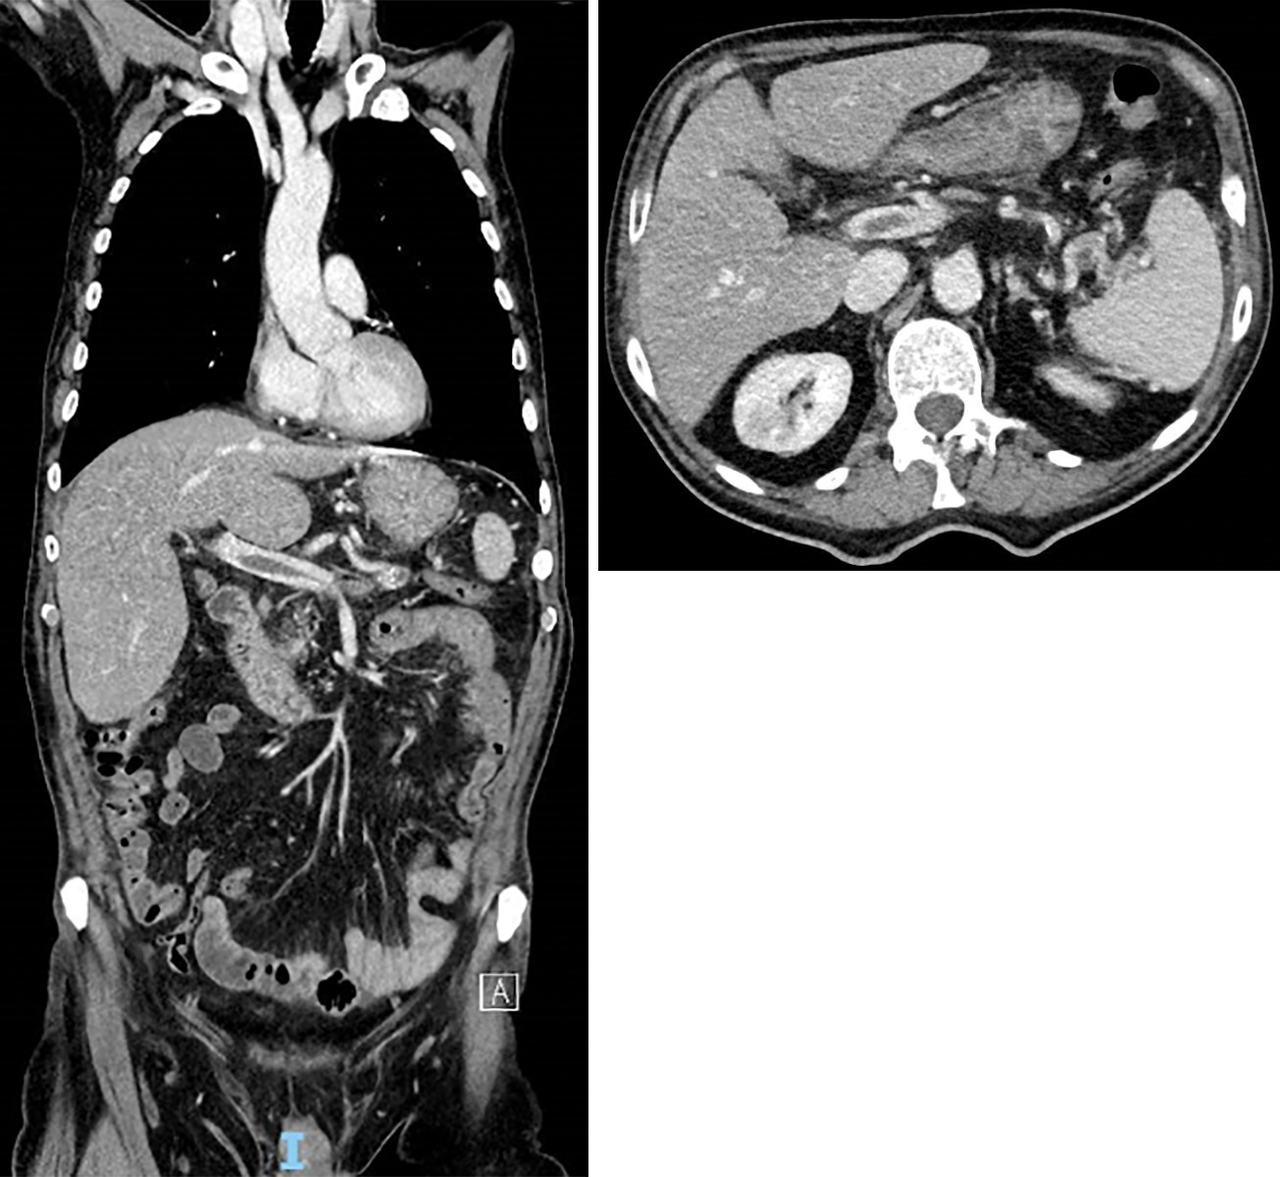

Homme de 67 ans, diabétique, consultant pour des douleurs abdominales.

Quel est votre diagnostic ?

Il s'agit d'une thrombose porte.